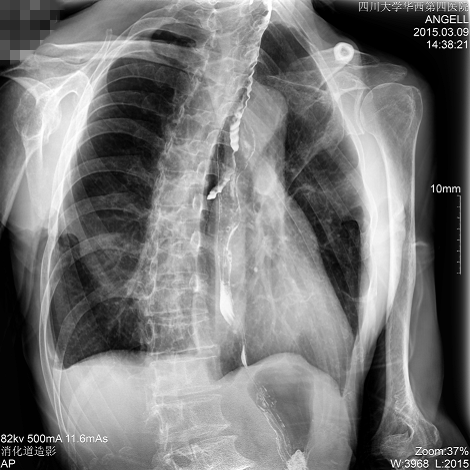

如下圖所示:該患者因吞咽時感到很難受,進食時也經(jīng)常咳嗽故就醫(yī)診斷。使用多功能dr為病人進行消化道造影診斷,要求他吞鋇后發(fā)現(xiàn),食道各段通過順利,形態(tài)規(guī)則,雙側(cè)梨狀窩不對稱左側(cè)稍淺,多次吞咽動作后,仍見鋇劑滯留,并見鋇劑進入氣管,屬于會厭征陽性。會厭功能紊亂,鋇劑進入了氣管。

圖為正位:通過動態(tài)影像可以清楚看到鋇劑進入了支氣管道且雙側(cè)梨狀窩不對稱

通過多功能dr可以診斷該病人的癥狀為會厭功能紊亂,鋇劑進入到了氣管。而在動態(tài)透視下可以清晰的觀察到鋇劑從何處進入氣管,可清晰顯示食管粘膜結(jié)構(gòu)。使用多功能dr其獨特的視頻采集技術(shù),可實時保存視頻并能實現(xiàn)900萬像素實時點片,才能獲取這樣清晰的病灶點。而常規(guī)dr只能拍攝靜態(tài)片,且成像效果大打折扣,因此較難確診病灶。